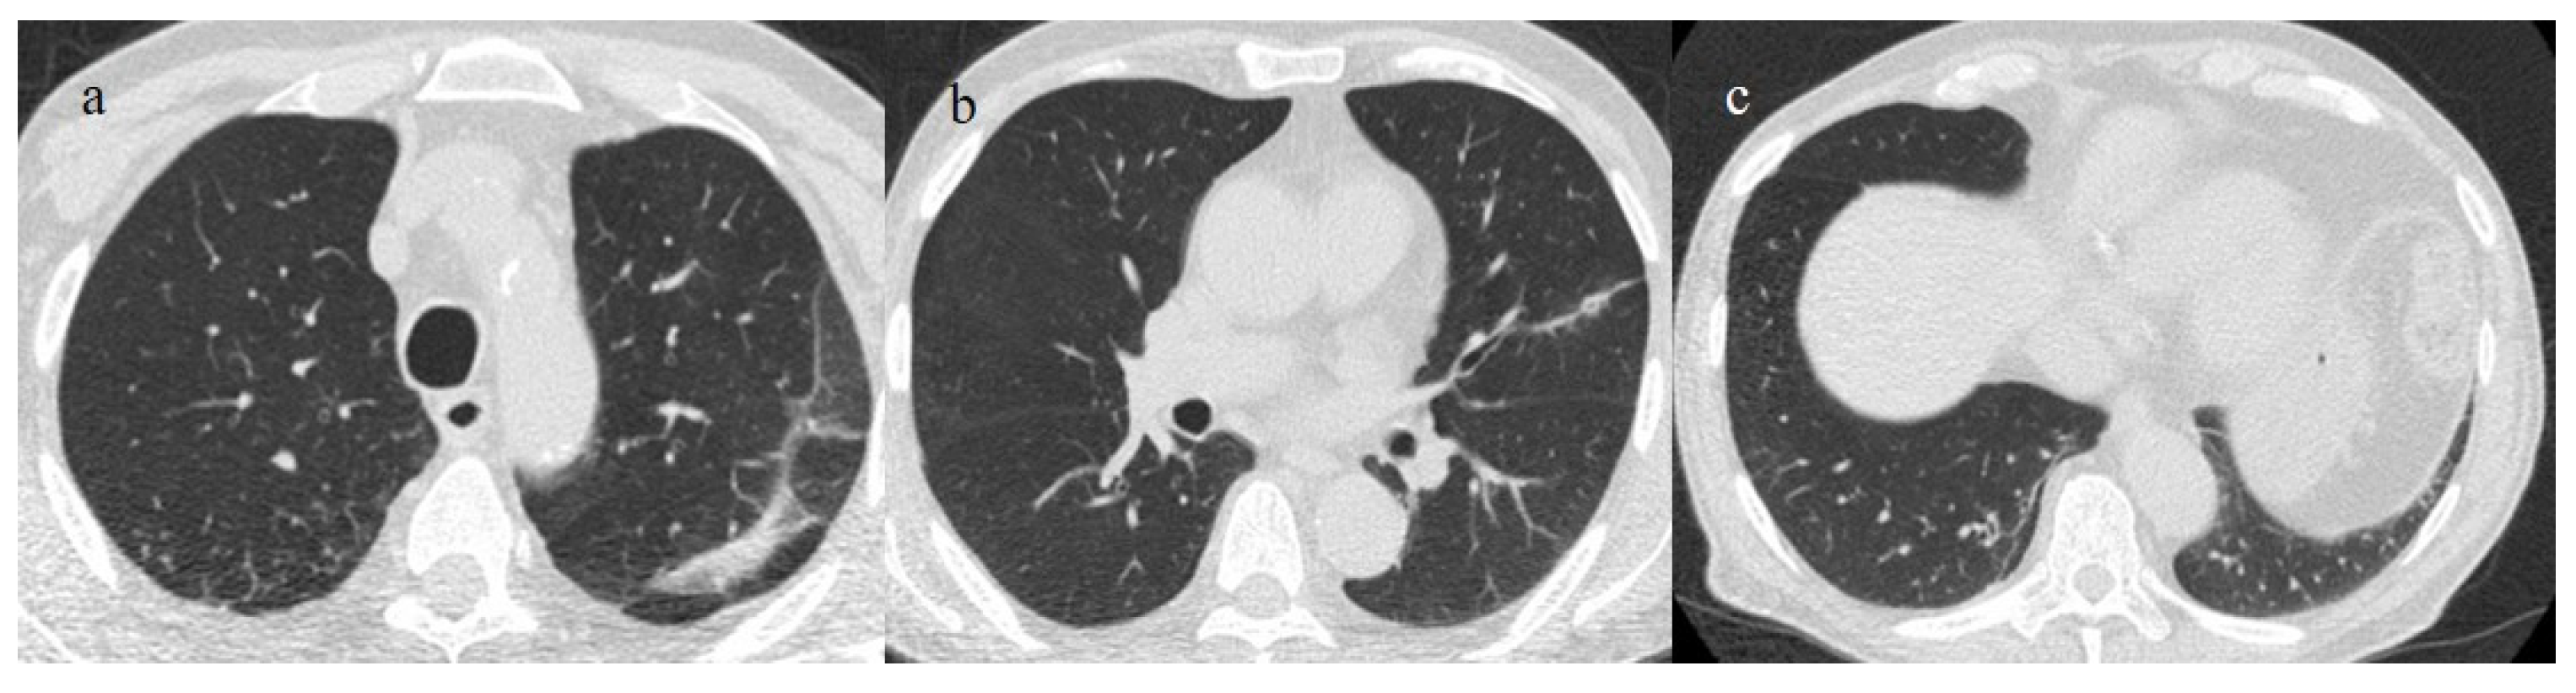

However, the Fleishner Society recommended the use of chest CT in emergency settings only for the triage of symptomatic COVID-19 patients presenting respiratory symptoms with a decline in O2 saturation level and patients at major risk of complications; it is not indicated to screen patients with COVID-19 [55]. At the beginning of the pandemic, Chinese radiologists described in detail the typical distribution of COVID-19 pneumonia, i.e., peripheral or peripheral and central. Ground glass opacities (GGOs) were visible in the early phase; as the pathology progressed, GGOs with a crazy-paving appearance and consolidations were evident along with subpleural and parenchymal bands. There was also a predominance of architectural distortion; in the peak stage, these findings had progressed, while the later stage demonstrated their resolution [55,56,57,58,59,60] (Figure 2).

Figure 2.

Chest CT COVID-19 pneumonia evolution during serial follow-up; (a) early phase with some GGO areas in a typical central and peripheral distribution; (b) the progressive phase with evolution in crazy paving with initial consolidation areas; (c) absorptive phase with reduction in previous inflammatory areas.

Other typical signs were vessel enlargements, the reversed halo sign, and subpleural curvilinear lines (Figure 1 and Table 1).